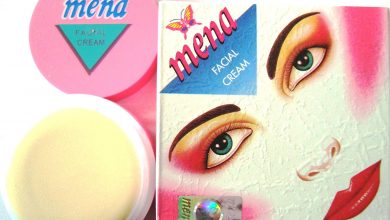

Popular facial cream has high mercury content, UAE health department warns

The Department of Health (DOH) in Abu Dhabi has advised users of facial cream, Mena Facial Cream, to stop using…